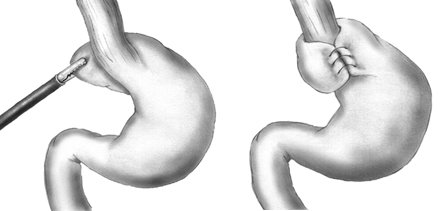

During the Nissen fundoplication, the upper part of the stomach is wrapped around the LES to strengthen the sphincter, prevent acid reflux, and repair a hiatal hernia.

Diagram of a Nissen fundoplication